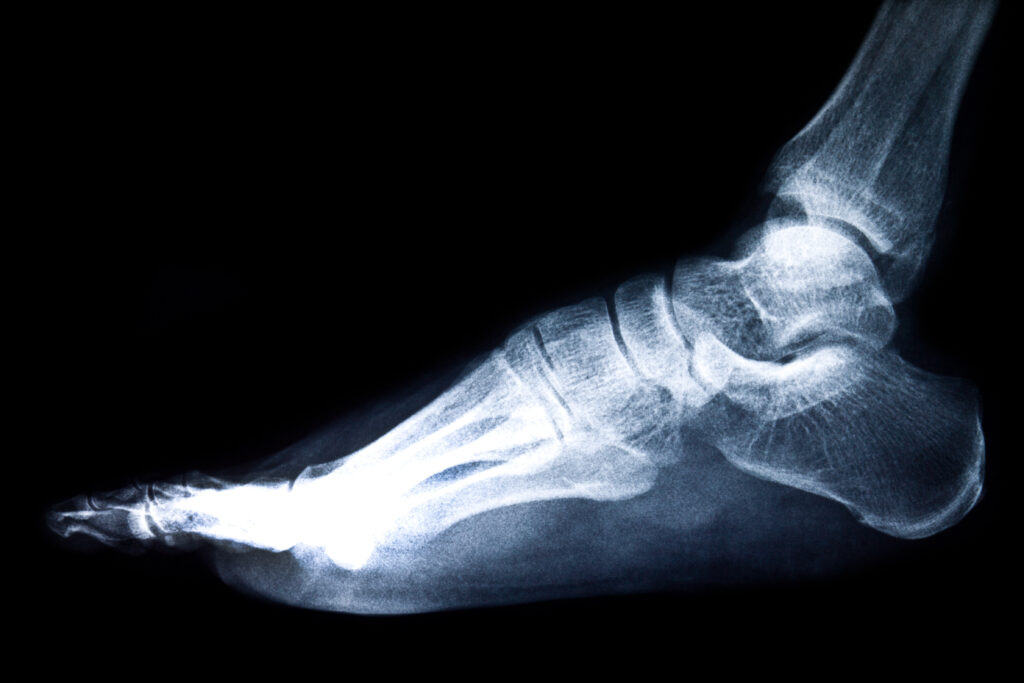

Lateral foot Digital X-Rays showing bones and arch structure for diagnostic evaluation

Digital X-rays are radiographic images used to identify injury, deformity, and disease affecting the bones and soft tissues of the body. At Alpine Foot Specialists in Lake Zurich IL, we offer in-office digital X-rays to provide immediate imaging and faster diagnoses for our patients. These images are also used to compare pre-operative and post-operative results and to monitor healing after surgery or fractures